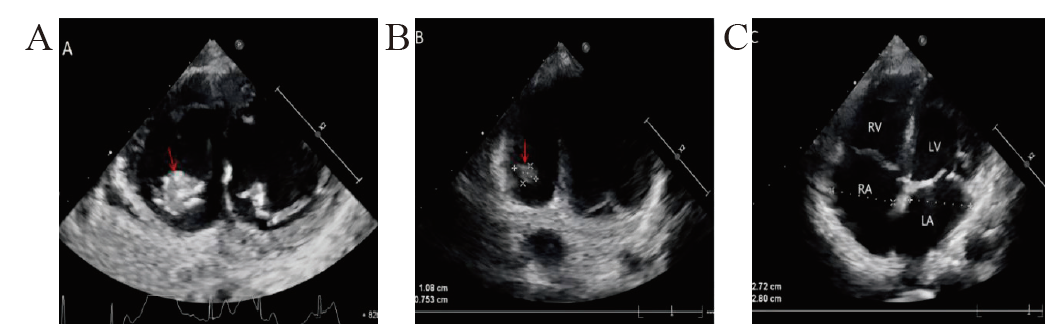

孙妍, 张宁, 张红菊, 等. 肺炎支原体肺炎合并右心室血栓超声特点分析及鉴别诊断[J]. 心肺血管病杂志, 2021, 40(12): 1234-1238.

|

Sun Y, Zhang N, Zhang HJ, et al. Ultrasonic features analysis and differential diagnosis of mycoplasma pneumoniae pneumonia complicated with right ventricular thrombus[J]. Xinfeixueguanbing Zazhi, 2021, 40(12): 1234-1238.

李奇蕊, 袁越, 林利, 等. 肺炎支原体肺炎并发心腔内血栓二例[J]. 中华儿科杂志, 2018, 56(12): 950-951.

Li QR, Yuan Y, Lin L, et al. Two cases of intracardiac thrombosis complicating mycoplasma pneumoniae pneumonia[J]. Zhonghua Erke Zazhi, 2018, 56(12): 950-951.

黄坤玲, 牛波, 路素坤, 等. 肺炎支原体肺炎并发心腔内血栓、肺栓塞1 例并文献复习[J]. 临床儿科杂志, 2021, 39(6): 421-424.

Huang KL, Niu B, Lu SK, et al. Mycoplasma pneumoniae pneumonia complicated with cardiac thrombus and pulmonary embolism: a case report and literature review[J]. Linchuang Erke Zazhi, 2021, 39(6): 421-424.